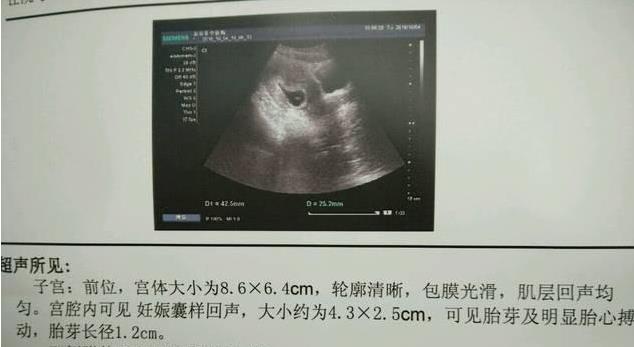

胎囊 胎芽 胎心到底是什么 育儿 品阅网

孕期胚胎大小对照表 快看胎宝宝发育正常吗

孕早期胚胎发育好不好 这几大关键指标给你答案

胎芽是什么样子 胎芽胎心是什么 豪友网

孕早期胚胎发育好不好 这几大关键指标给你答案 网易订阅

试管婴儿移植成功后 孕囊 胎心 胎芽多久能看见 知乎

孕囊 胎芽 胎心代表什麼 捉摸不定的胎心胎芽 什麼時候出現 壹讀

孕5周 孕囊大小的标准值是多少呢 孕妈不妨自

孕囊是什麼 孕囊大小看男女靠譜嗎 每日頭條

孕早期b超能告诉我们什么 知乎

懷孕 孕囊 是怎麼變化的 孕囊 發育慢怎麼辦 每日頭條

孕早期孕囊 胚芽 胎心完美三部曲 每日頭條

孕6周胎芽發育簡報 B超單上寫有這 四物 表明 坐胎 穩定 每日頭條